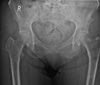

What is the preferential location of multiple myeloma?

A

• vertebrae

• skull

• ribs

• pelvis

• femur

What are the early stage imaging findings of multiple myeloma?

- normal radiographs - diffuse/generalized osteopenia (1st radiographic sign) - possible insufficiency/fatigue Fx

26

What are the late stage imaging findings of multiple myeloma?

- permeative or moth-eaten osteolysis (as osteoblasts are inhibited) - vertebral collapse - sparing of pedicles (no winking owl or blind vertebra) - bone scan often normal